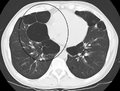

A chest X-ray is not useful to establish a diagnosis of COPD but it is of use in either excluding other conditions or including comorbidities such as pulmonary fibrosis and bronchiectasis. Characteristic signs of COPD on X-ray include hyperinflation (shown by a flattened diaphragm and an increased retrosternal air space) and lung hyperlucency.[5] A saber-sheath trachea may also be shown that is indicative of COPD.[110]

A severe case of bullous emphysema

Axial CT image of the lung of a person with end-stage bullous emphysema